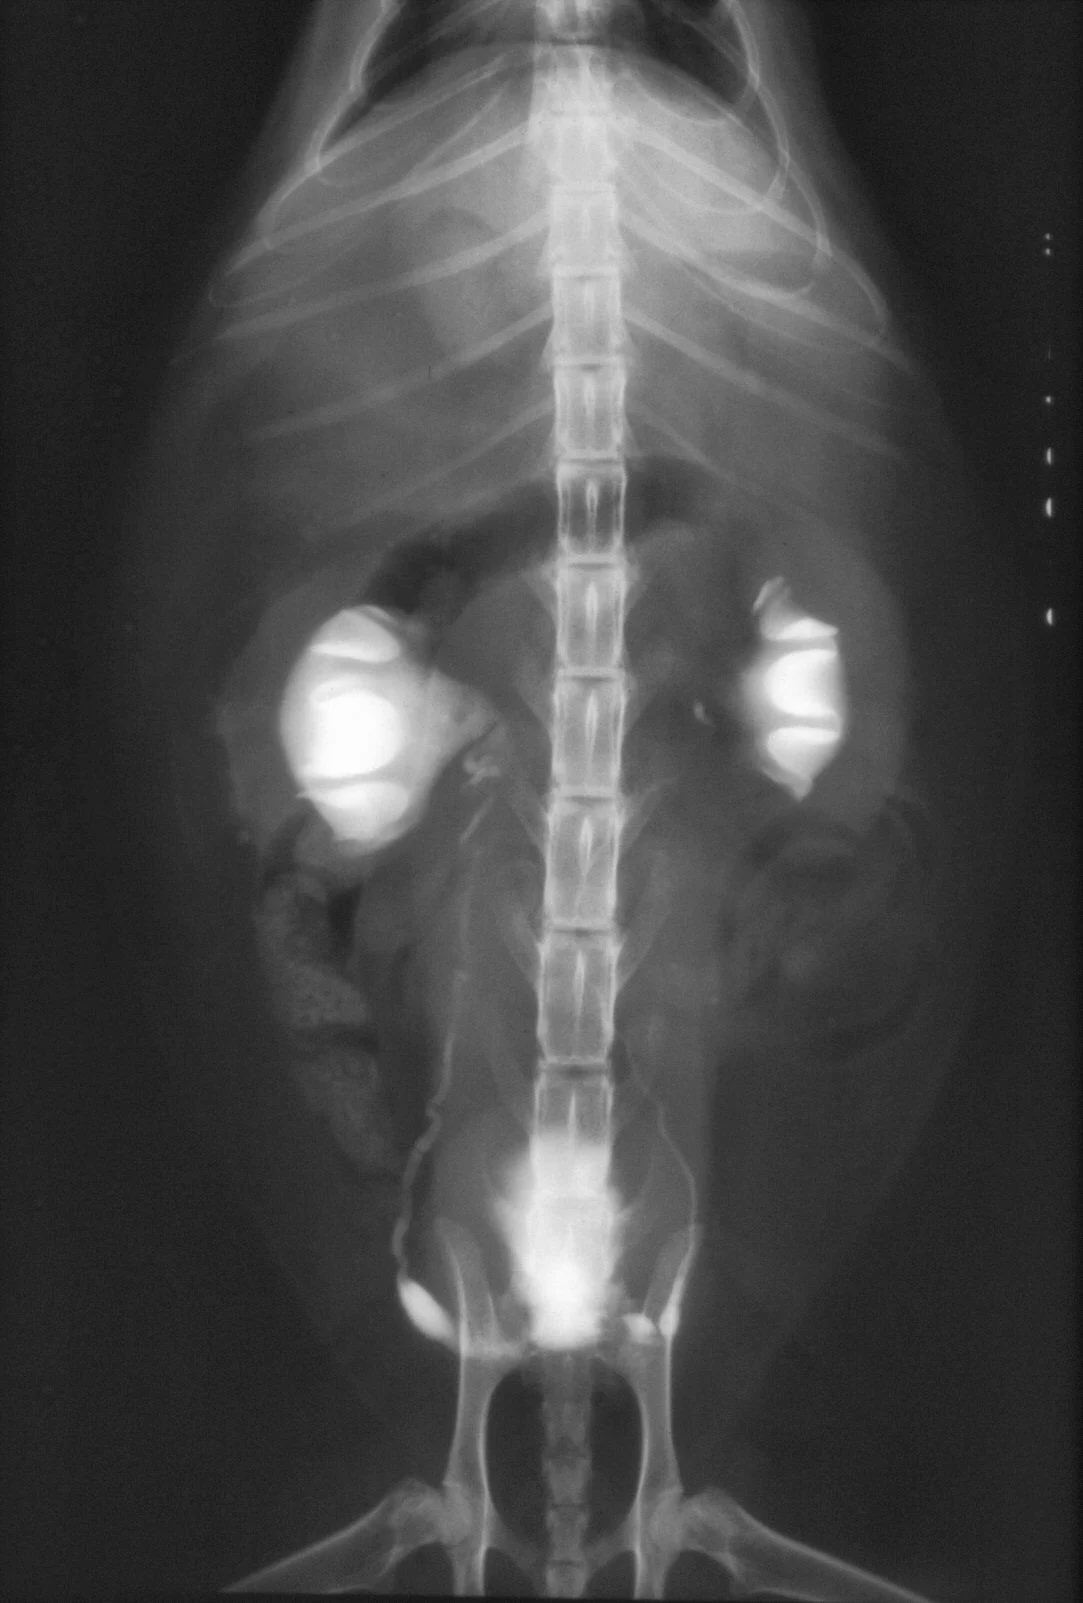

Abdominal radiographs will show only an enlarged kidney or kidneys (Figure 2A), but excretory urography will show renal pelvis dilatation (Figure 2B). Ultrasonography will also show hydronephrosis, renal parenchymal disarray, and necrotic debris in the renal collecting system (Figure 3).

Abdominal radiographs of a cat with bilateral pyonephrosis; a cystotomy performed 6 months previously had caused bilateral ureteral obstruction at the urethral junction (A and B). Pyelography was done by pyelocentesis, and bilateral hydronephrosis is shown.